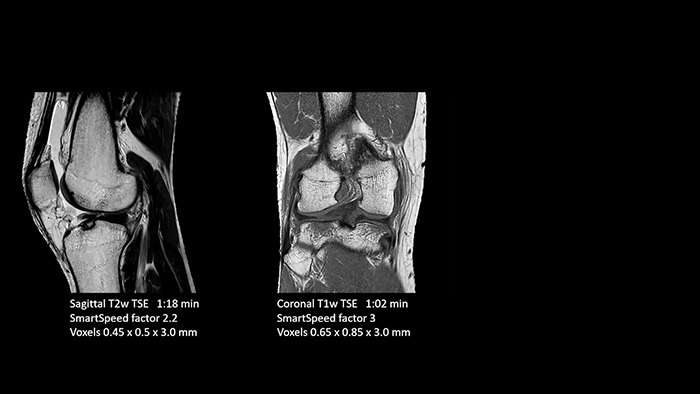

Previously, the practice wasn’t able to use 3D imaging on all joints, because the time required was too long, and on some joints it was simply not possible to achieve a good quality image, Dr. Schröter says. “Now, with SmartSpeed we consistently use 3D imaging for all joints and can thus discover the smallest changes, for example in the cartilage. And that, of course, helps us in making a detailed diagnosis.” Dr. Schröter says their MSK images show high contrast and extremely high quality. He mentions the menisci as an example. “We use a 3D proton density weighted fatsat sequence, thickness is 0.3 mm and scan time 3 minutes. The MPRs show an unbelievable resolution. Very small tears and even fraying of the tip of the meniscus become visible, which is normally only possible in arthroscopic surgery. When imaging the small joints of the fingers and the thumb we achieve extraordinary quality. Using SmartSpeed we succeed in displaying even very small structures anatomically correct, enabling us to see the extent of possible injuries. Tendons and ligaments appear with higher resolution so we can better see the injury pattern and describe and delimit it. Our referring physicians are fascinated by the extraordinary quality and high level of detail of the images. Patients are happy that the examination does not take too long. We hear from patients that it took a lot less time than they expected. This is especially important when scanning patients who are very uncomfortable in the MRI environment.”

With these 3D scans we can create freely selectable MPRs that are pin-sharp, allowing us to easily see pathological changes.”